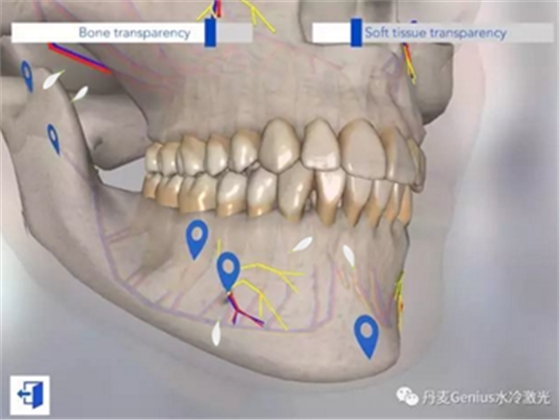

上頜表麻的注射位點(diǎn)

下頜表麻的注射位點(diǎn)

以上視頻來(lái)自加拿大的哥倫比亞學(xué)院的牙科分校的教學(xué)視頻。如果還是覺(jué)得困難,也可以在iPad上下載一個(gè)牙科麻醉注射的AR模擬器,慢慢找位置。第三行,第一列。